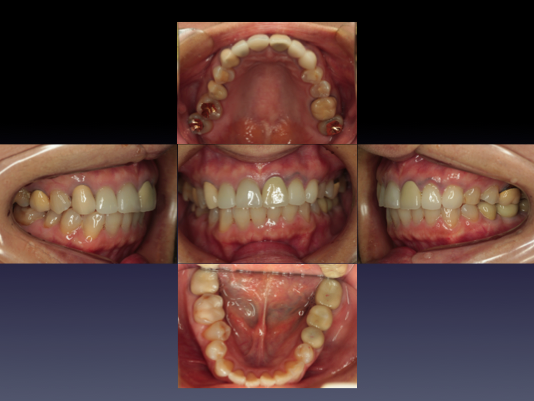

症例⑤

上左右の奥歯を失ってしまったため、保険の入れ歯を入れたが、違和感が強く、しっかり噛むことができないため、インプラントを併用した入れ歯を作ることで違和感なく、しっかり噛むことができるようになった。 また通常の入れ歯は、はずれないようにするため金属のバネを歯に引っ掛けるため見た目も悪いが、インプラントによって固定されているためバネもなく、見た目も非常に良いものとなっている。

-

術後レントゲン写真